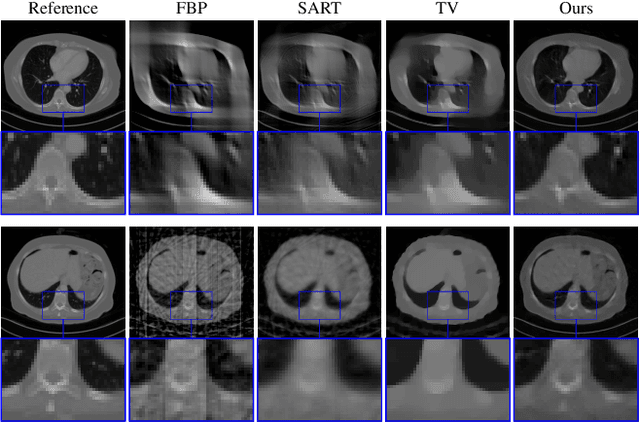

In the past decades, Computed Tomography (CT) has established itself as one of the most important imaging techniques in medicine. Today, the applicability of CT is only limited by the deposited radiation dose, reduction of which manifests in noisy or incomplete measurements. Thus, the need for robust reconstruction algorithms arises. In this work, we learn a parametric regularizer with a global receptive field by maximizing it's likelihood on reference CT data. Due to this unsupervised learning strategy, our trained regularizer truly represents higher-level domain statistics, which we empirically demonstrate by synthesizing CT images. Moreover, this regularizer can easily be applied to different CT reconstruction problems by embedding it in a variational framework, which increases flexibility and interpretability compared to feed-forward learning-based approaches. In addition, the accompanying probabilistic perspective enables experts to explore the full posterior distribution and may quantify uncertainty of the reconstruction approach. We apply the regularizer to limited-angle and few-view CT reconstruction problems, where it outperforms traditional reconstruction algorithms by a large margin.